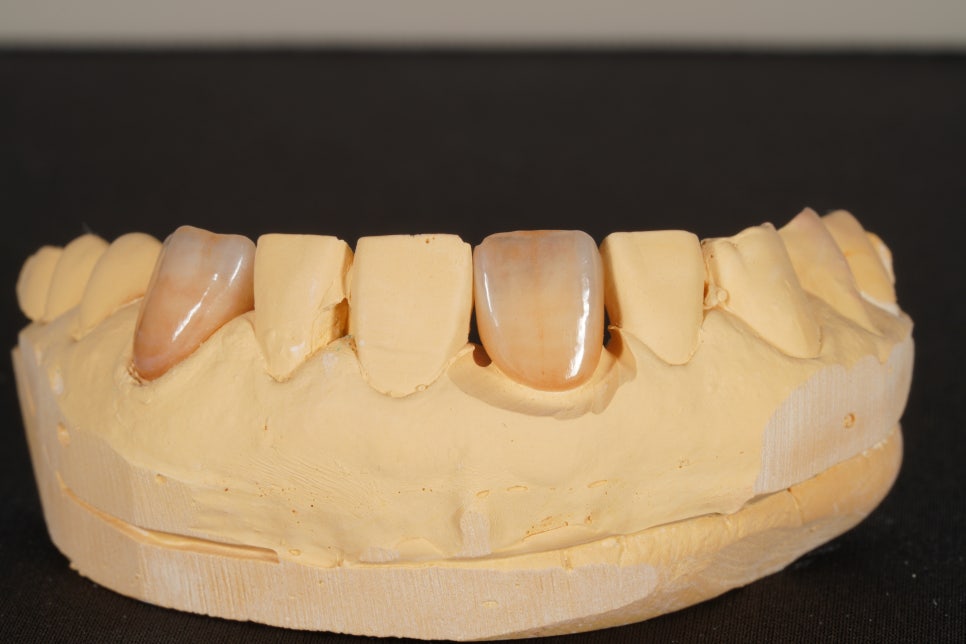

기공사님께서 고생하셔서

이렇게 멋진 크라운을 만들어주셨는데요

크라운만 받아봐도 감이 옵니다.

"아 이거 잘 맞을 것같다"

이렇게 만들기 위해서는

환자분 치아의 색상을 최대한 잘 전달하기 위해

치료를 시작하기 전에

치아가 물기를 머금고 있는 상태에서

색상 사진을 찍는 것이 중요합니다.